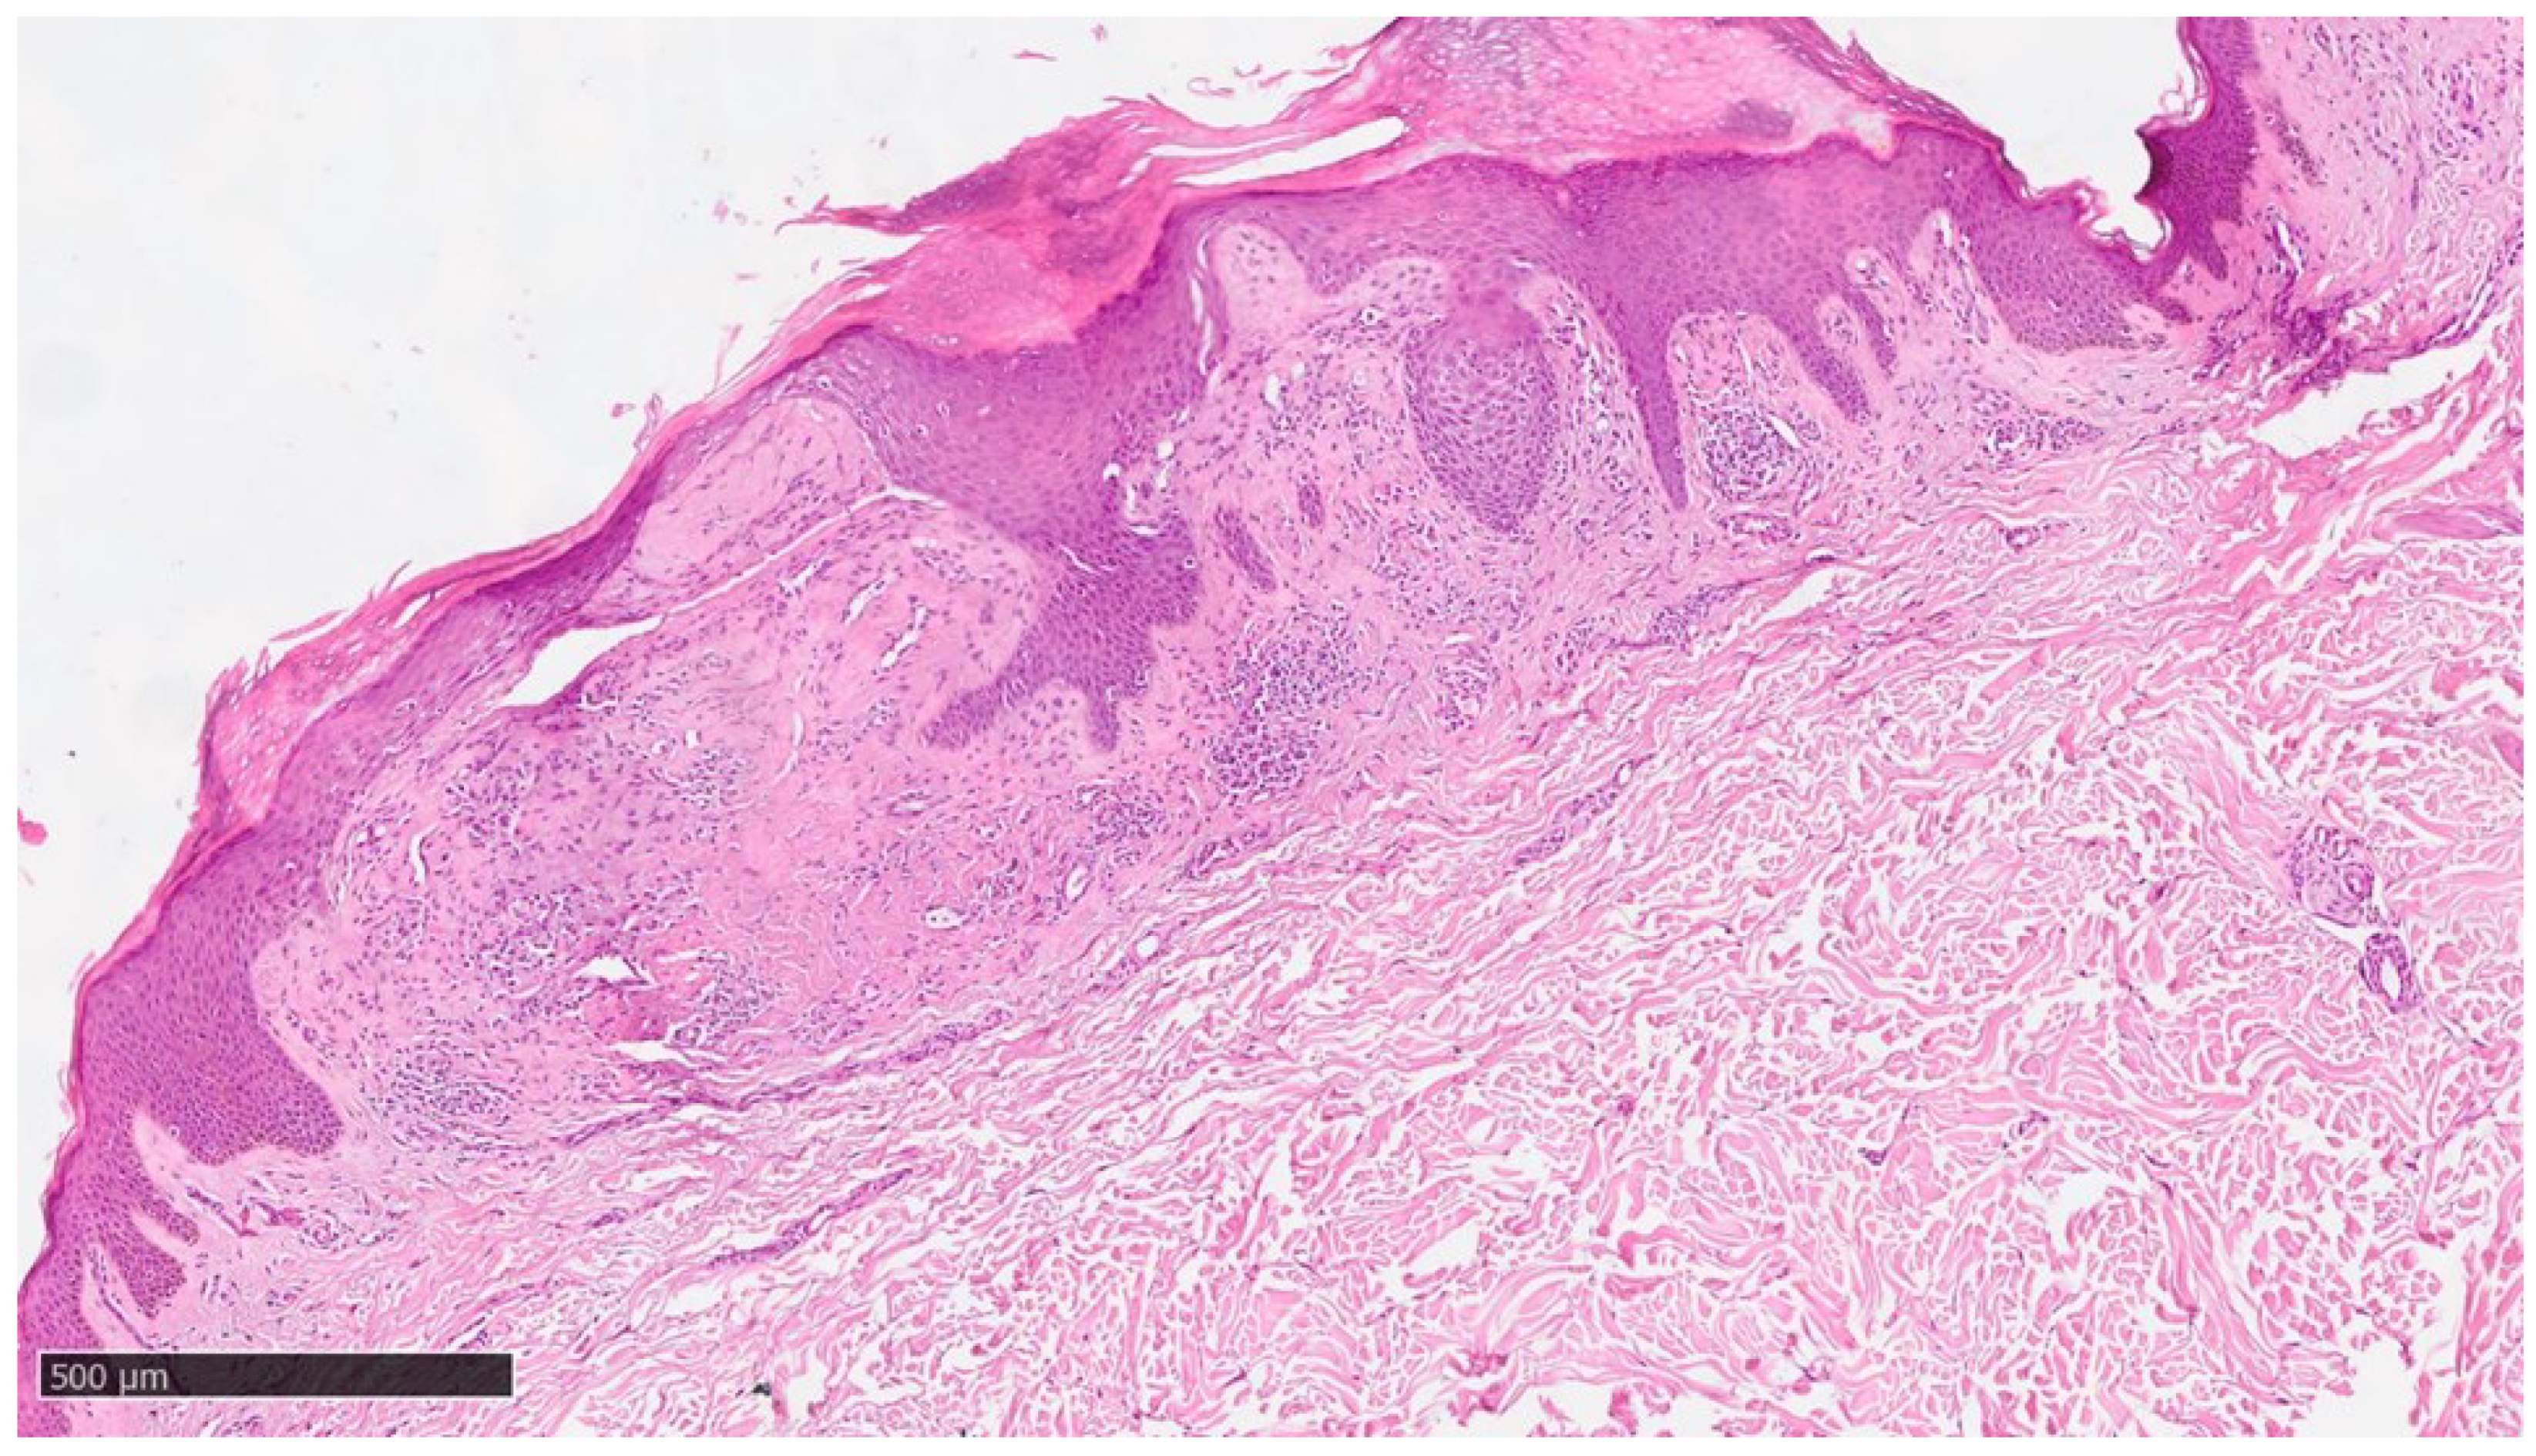

At our clinic for a diagnosis of certainty of LA, an incisional biopsy was performed at typical infiltrated plaques on the lower limbs. The histopathological investigations reported typical LA findings such as deposition of amyloid material at the papillary dermis, beneath to dermo-epidermal junction; there were also some areas with incontinence of melanic pigment and diffuse inflammatory infiltrate at the middle and superficial dermis. The epidermis was not interested by this infiltration and acts as an innocent bystander with acanthosis, hyperkeratosis and elongation of the epidermal ridges (Figure 3 , Figure 4 and Figure 5).

Figure 2. Condition of the patient after one year of Dupilumab therapy showing skin smooth and free of lesions with mild dyscromic aftermaths.Figure 3. Histological photomicrograph showing an area with hyperkeratosis, some degree of acantosis and amyloid deposition in the papillary dermis (Hematoxylin-Eosin, Original Magnification 4x).

Figure 3. Histological photomicrograph showing an area with hyperkeratosis, some degree of acantosis and amyloid deposition in the papillary dermis (Hematoxylin-Eosin, Original Magnification 4x).